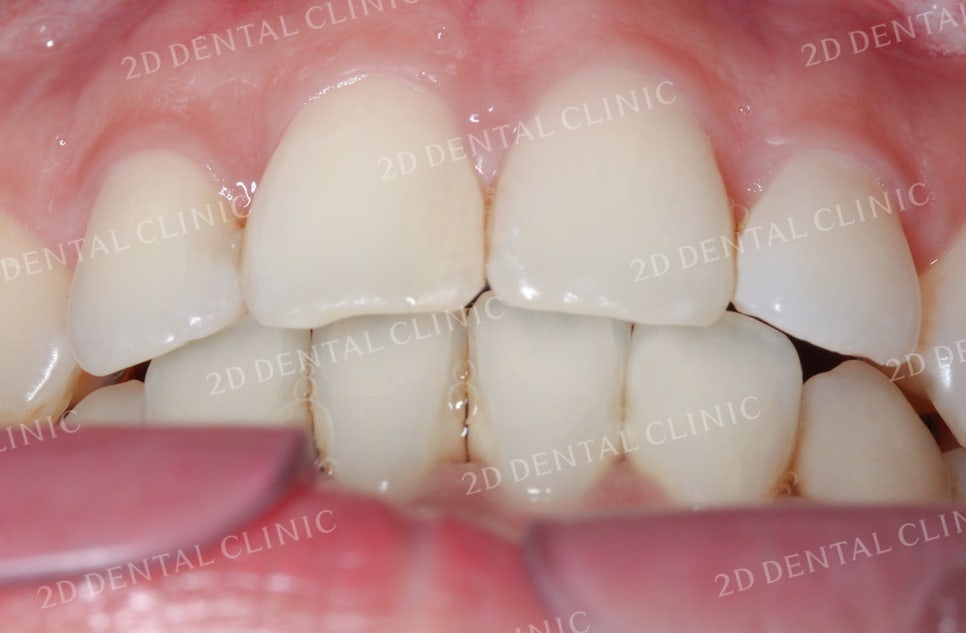

비대칭 돌출앞니 전체교정 전

투디치과(2D치과)

비대칭앞니, 돌출앞니를 전체교정으로 교정하고 싶다면!? by.투디치과(2D치과)

좌우의 안모 사진입니다.

표시된 부분에서 완전히 맞물리지 못한

치아 사이의 틈이 발견되고 있네요.

이러한 교합면 사이의 빈 공간은

음식물 섭취 시 불편을 유발하는 원인 중 하나입니다.